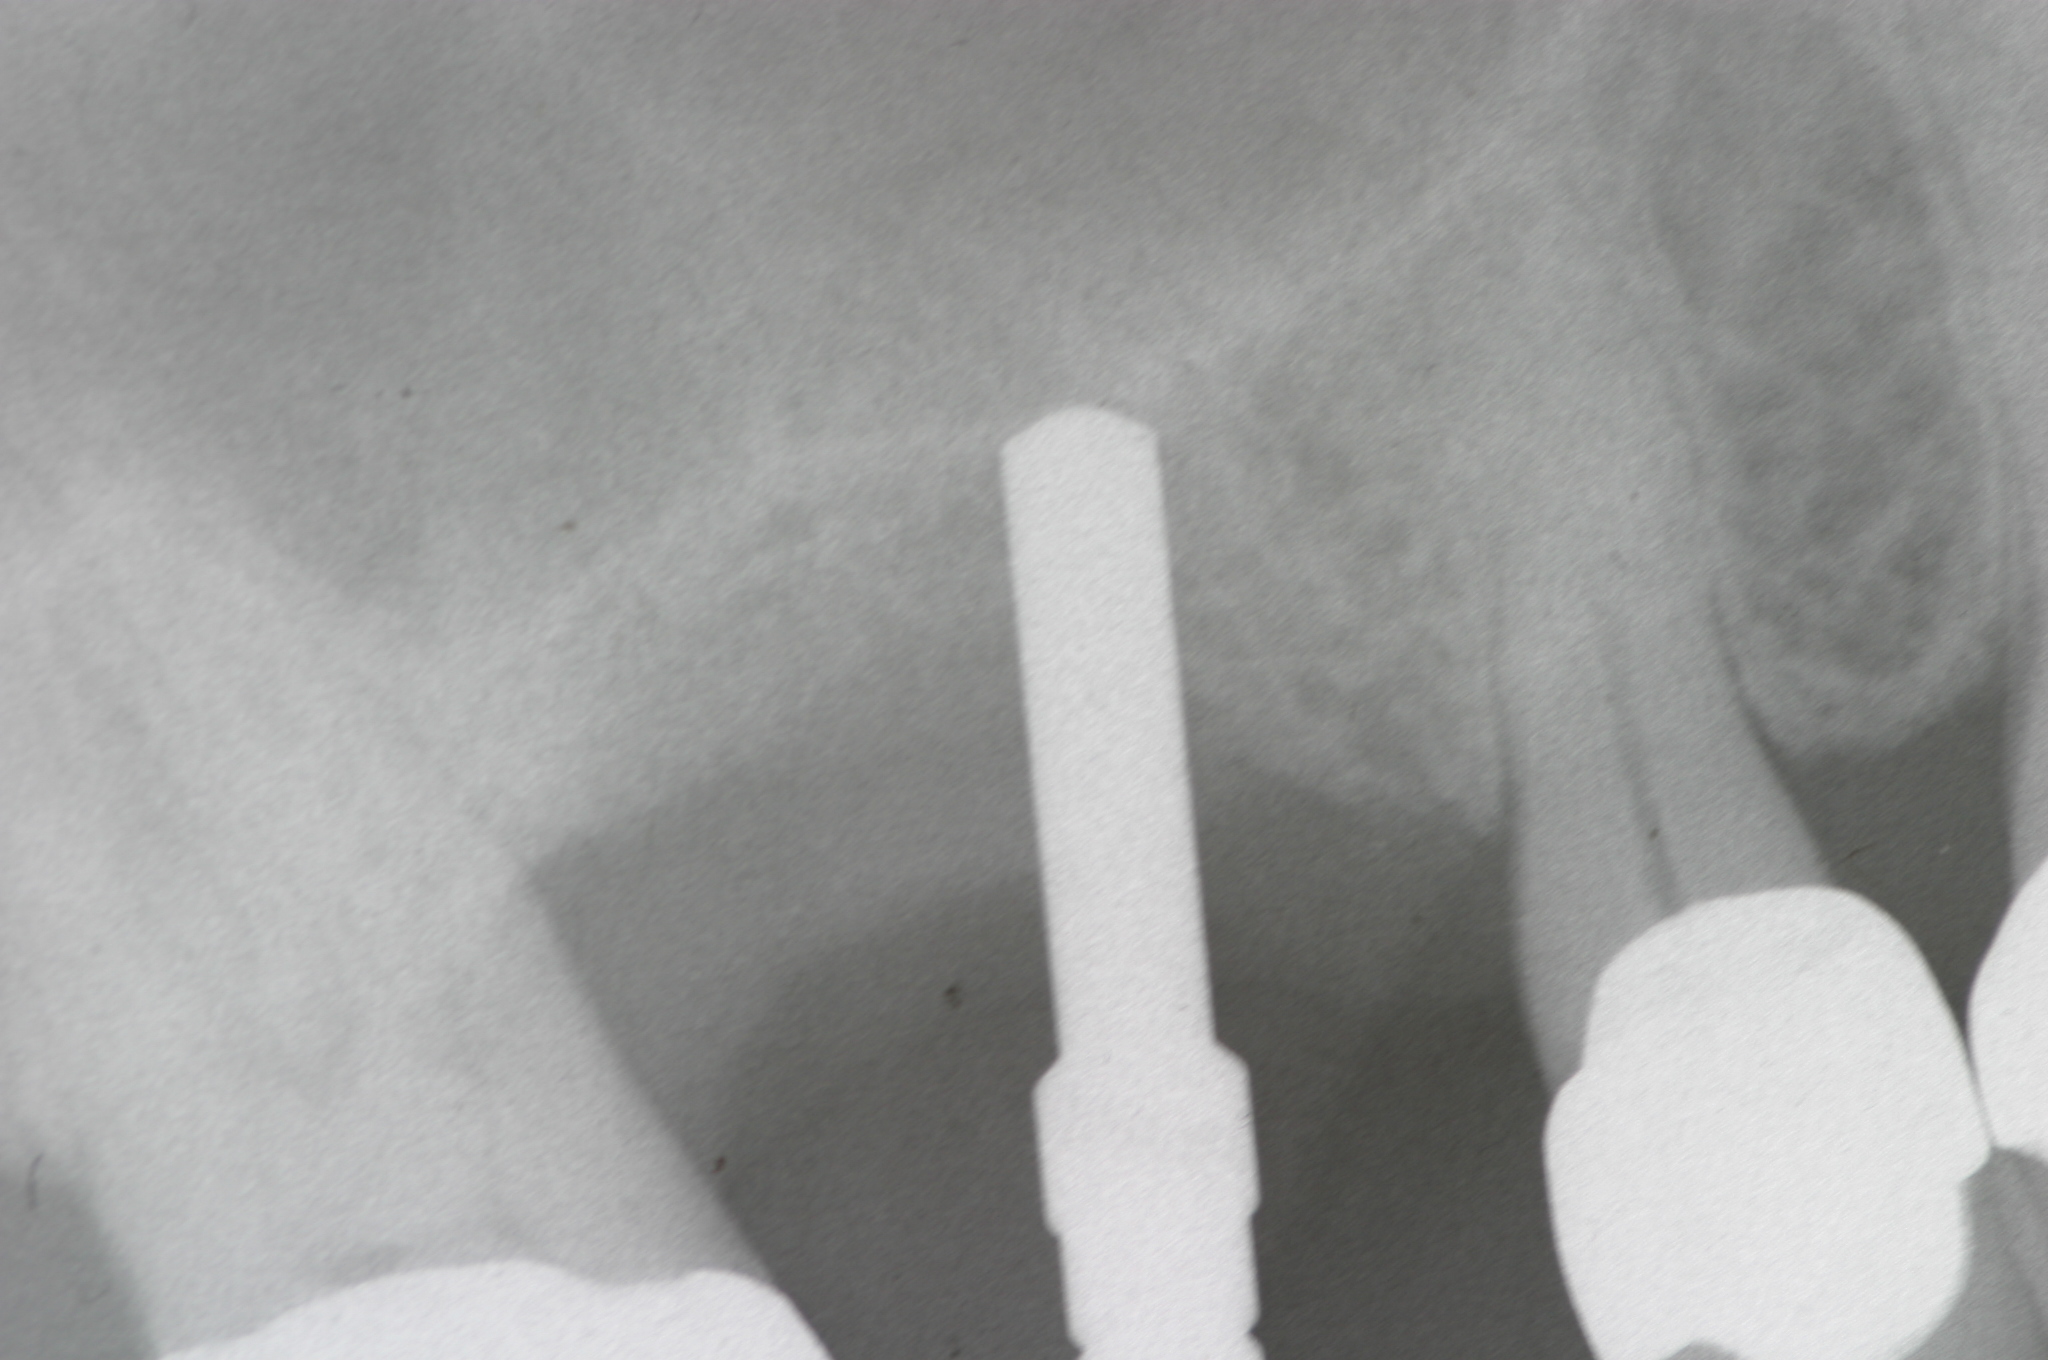

This patient was a 73-year-old man with only about 3.5 mm of native bone in the No. 3 site (Figure 20). The composite graft used here was a 50:50 mixture of DFDBA and deproteinized bovine bone mineral (Osteohealth, www.osteohealth.com) with approximately 40% calcium sulfate added. The implant was the same type and length as in Case 1 above. Figure 21 shows the area on the day of placement. In the CBCT scan on the day of placement (Figure 22), the native bone and bone graft were clearly discernable. However, the postoperative radiograph taken at 6.5 months (Figure 23) showed no marginal bone loss and a significantly denser appearance than when the graft was place. The membrane was raised about 7 mm to 8 mm. The final radiograph was taken after extraction of tooth No. 2 and after extraction of tooth No. 4 and immediate implant placement.

Case 3. Preoperative radiograph showing about 3.5 mm of ridge height.

Fig. 20

Day of sinus augmentation and implant placement in the No. 3 position. The sinus membrane has been raised about 7 mm to 8 mm.

Fig. 21

CBCT scan (Kodak 9000D) of No. 3 area, day of placement. Appearance of native bone and bone graft is clearly discernable.

Fig. 22

A 6.5-month postoperative radiograph. Teeth Nos. 2 and 4 have been extracted and an immediate implant had been placed in the No. 4 position.

Fig. 23